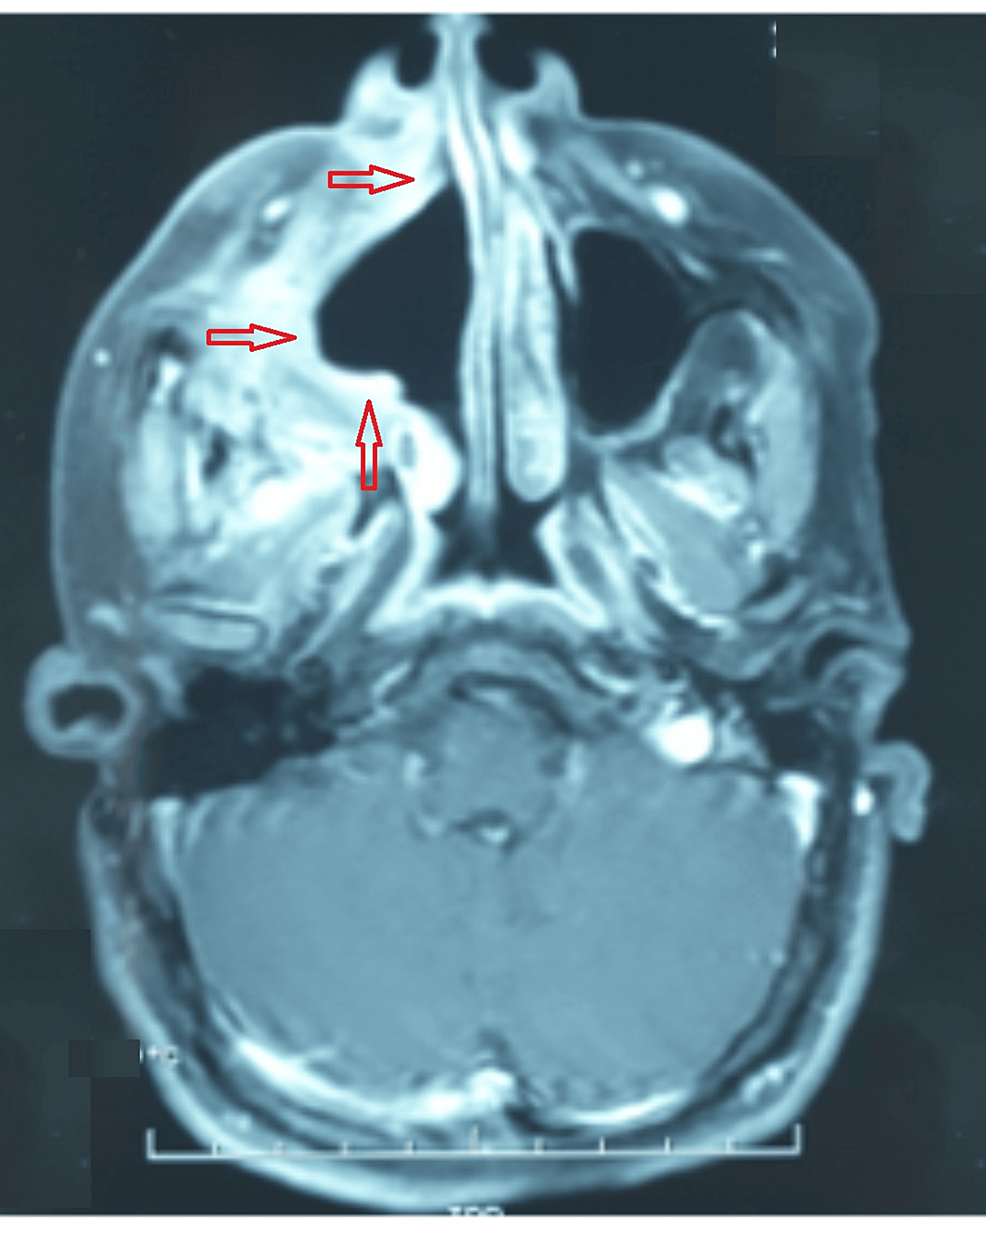

(PDF) Maxillary Sinus Ameloblastoma in Turner syndrome A Comprehensive Ameloblastoma Follow Up Peripheral ameloblastoma may involve soft tissues without invasion or. Ameloblastoma is a benign lesion of the jaws with a locally invasive course and high. Ameloblastoma is the most common benign, but locally destructive, epithelial odontogenic tumour. The most frequently performed treatment option was enucleation plus curettage/peripheral ostectomy in 94 ameloblastomas, followed by. The average period of follow up was 6.2. Ameloblastoma Follow Up.

Cureus Maxillary Sinus Ameloblastoma in Turner Syndrome A Ameloblastoma Follow Up Ameloblastoma is a benign lesion of the jaws with a locally invasive course and high. Ameloblastoma is the most common benign, but locally destructive, epithelial odontogenic tumour. Peripheral ameloblastoma may involve soft tissues without invasion or. The average period of follow up was 6.2 years. Keeping patients informed of the importance of regular follow up is crucial to. Ameloblastoma is. Ameloblastoma Follow Up.

Cureus Maxillary Sinus Ameloblastoma in Turner Syndrome A Ameloblastoma Follow Up Keeping patients informed of the importance of regular follow up is crucial to. Ameloblastoma is a benign lesion of the jaws with a locally invasive course and high. Peripheral ameloblastoma may involve soft tissues without invasion or. The most frequently performed treatment option was enucleation plus curettage/peripheral ostectomy in 94 ameloblastomas, followed by. The average period of follow up was. Ameloblastoma Follow Up.